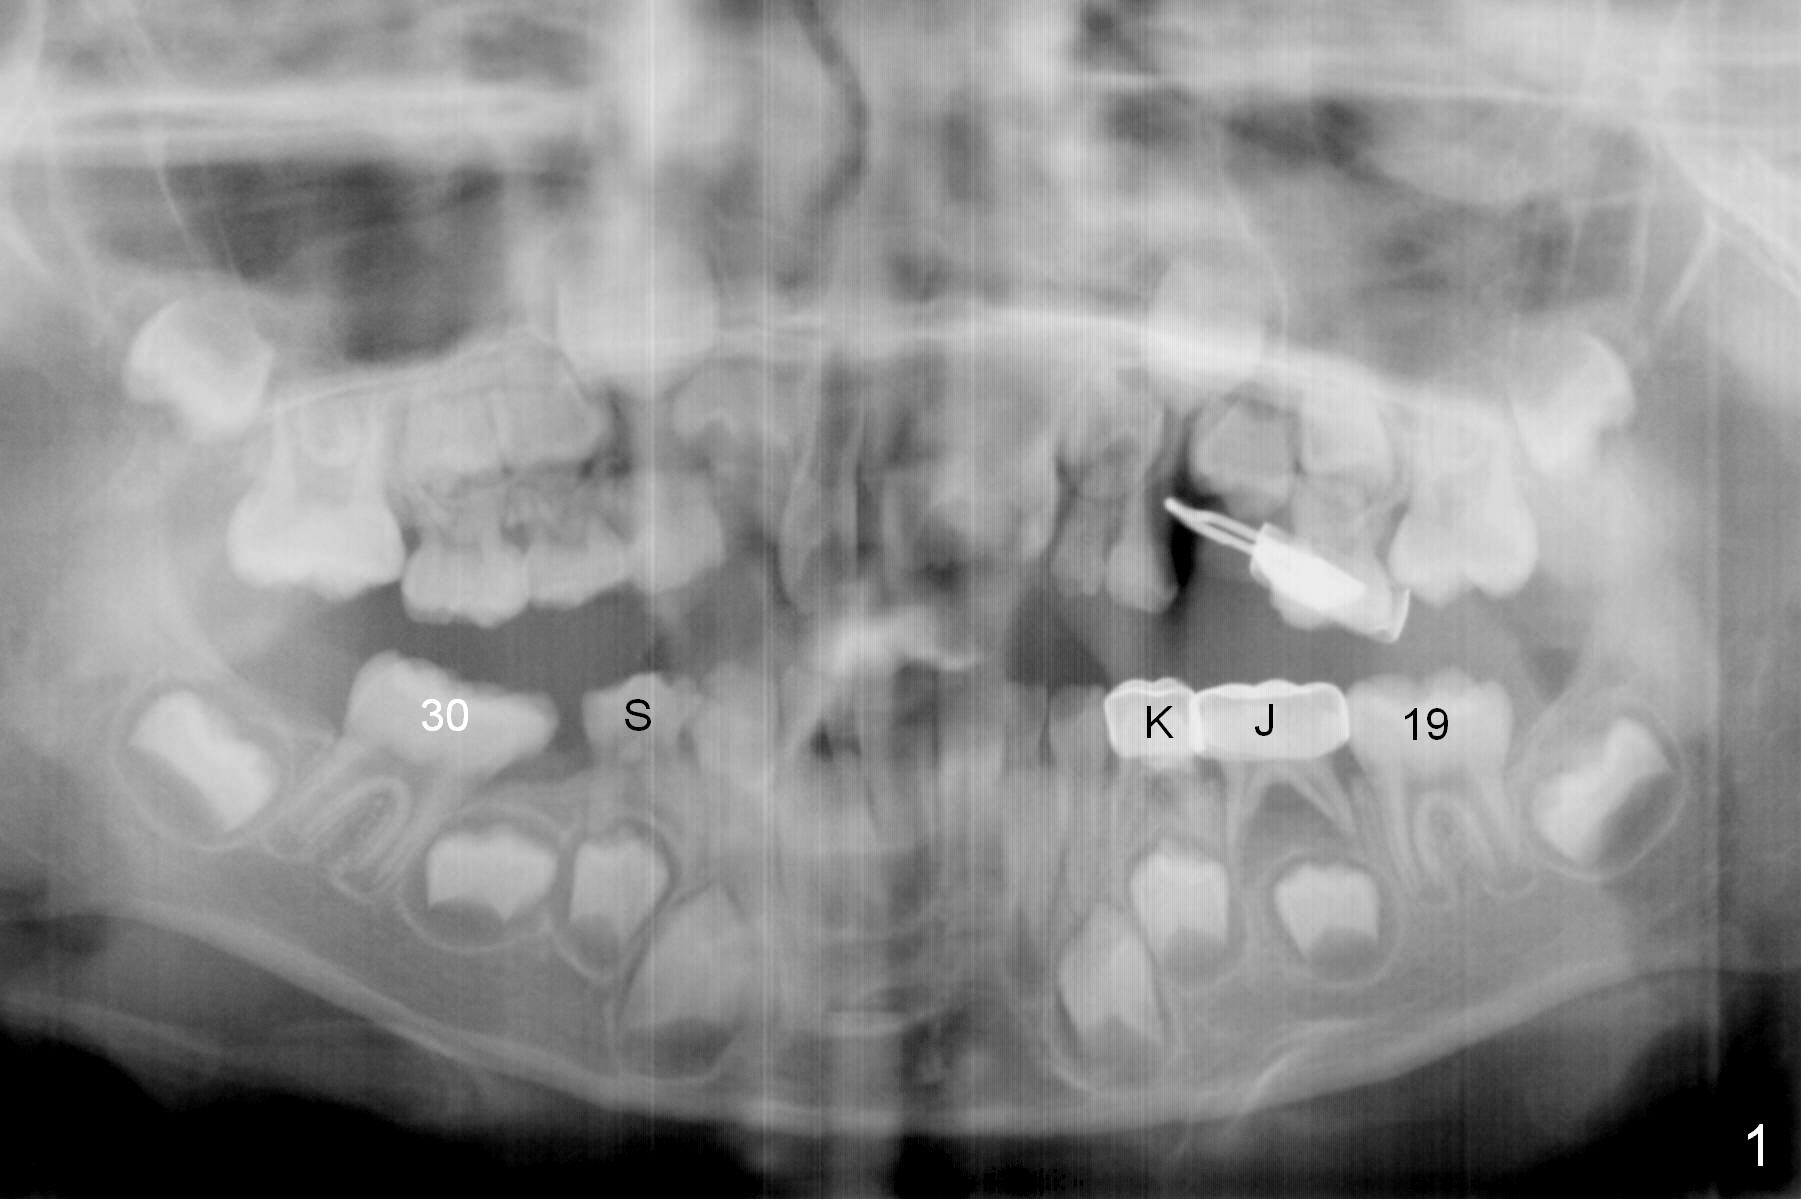

At age of 6 years 1 month, Linwei (boy) has crowding problem, especially in the lower right quadrant (Fig.1). At 9, the crowding also involves the upper right and lower left quadrants (Fig.2). A bilateral space regainer is placed for the lower arch a month later.